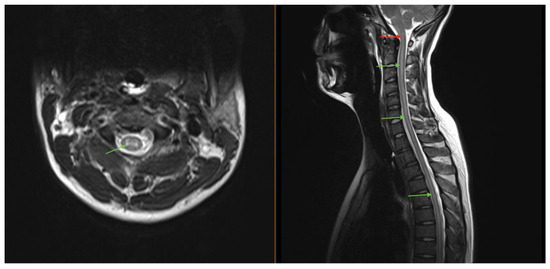

Magnetic resonance imaging (MRI) of the brain/total spine revealed longitudinally extensive gray-matter predominant myelitis of the entire spinal cord (Figure 2) and patchy T2-FLAIR hyperintensities in the brain (corona radiata and splenium), suggestive of inflammatory encephalomyelitis. Lumbar puncture (LP) showed an opening pressure of 27 cm H2O, 388 nucleated cells with lymphocytic predominance, and a protein 197 mg/dL. Several viral and autoimmune panels (including Aquaporin-4, herpes, and paraneoplastic antibodies) were negative in the cerebrospinal fluid (CSF), except for a positive CSF myelin oligodendrocyte glycoprotein (MOG) antibody titer that was performed on a research basis. A corresponding MOG panel in the serum resulted at 1:20. The diagnosis of MOG-associated disease (MOGAD) was made.

Figure 2. MRI imaging of our patient who was found to have a longitudinally extensive gray matter lesion (green arrows) extending cranio-caudally from the brainstem through the lumbar spinal cord. The lesion involvement of the dorsal medulla (red arrow) was thought to represent the pathologic etiology of the DBN seen in our case.